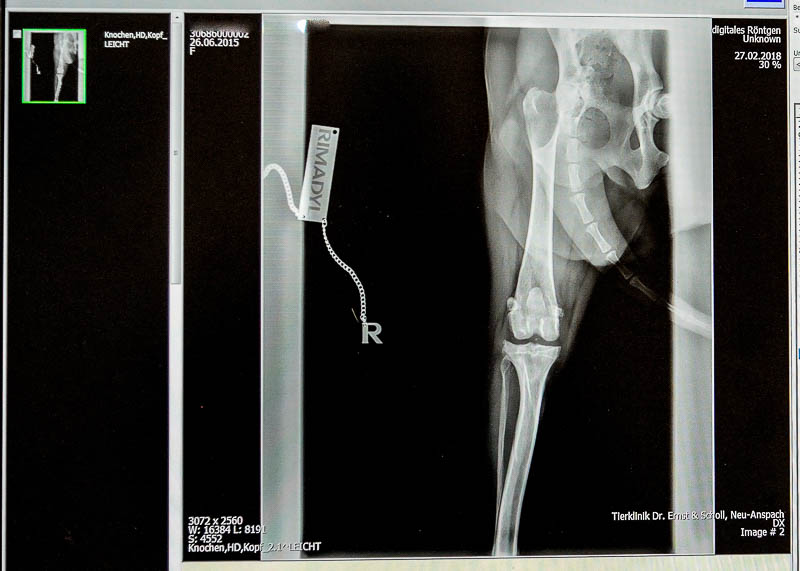

Mit unserer modernen digitalen Röntgenanlage sind wir in der Lage die vielfältigsten Erkrankungen sowohl der Knochen als auch der Weichteile bildlich darzustellen. Die Röntgenbilder brauchen keine Entwicklungszeit stehen sofort zur Auswertung am Computer bereit.

Die Speicherung der Bilder erfolgt im sogenannten DICOM Format. Das bedeutet, die Bilder sind juristisch anerkannt und können nicht mehr nachträglich manipuliert werden.

Ein weiterer großer Vorteil digitalen Röntgens ist die wesentlich geringere Strahlenbelastung für Mensch und Tier. Es besteht auch die Möglichkeit die Bilder auf DVD zu brennen oder auch per E-Mail an Sie oder an Kollegen zu schicken.